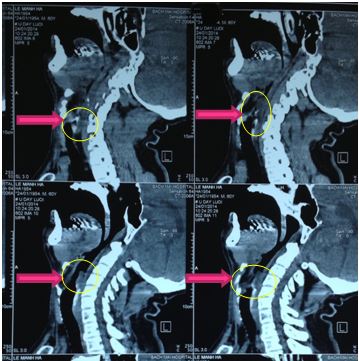

Chụp cắt lớp vi tính 64 dãy vùng hầu họng:

+ Khối sùi vị trí đáy lưỡi thanh thiệt kích thước 32x24mm, bờ không đều, ranh giới không rõ, tỷ trọng mô mềm, ngấm thuốc mạnh sau tiêm (46-83HU), khối dính một phần vào sụn nắp thanh môn, lồi vào lòng thanh quản gây hẹp lòng thanh quản, vị trí hẹp nhất 4mm, chưa phát triển xâm lấn vào xoang lê hai bên.

+ Hạch to vùng cổ hai bên dọc bó mạch cảnh, khối hạch lớn nhất bên phải 20x12mm, bên trái 26x17mm, hạch ngấm thuốc mạnh sau tiêm

Kết luận: Hình ảnh khối u sùi vị trí hố đáy lưỡi thanh thiệt, hạch to vùng cổ hai bên.

Hình 2. Hình ảnh khối u trên hình ảnh cắt lớp vi tính 64 dãy vùng hầu họng